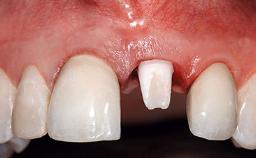

A 32-year-old female Caucasian patient with a compromised maxillary right central incisor was referred to us by a general dentist. Her chief complaints were discomfort and mobility of tooth 11 with unsatisfactory esthetics due to discoloration. The patient reported a previous trauma, some years earlier, as the origin of pathology on the afflicted tooth. Anamnesis was negative for any other dental or periodontal pathology in the remaining dentition. The patient did not take any medication and reported to be a light smoker (5–10 cigs/day). She had high esthetic expectations of her treatment. The extraoral examination revealed a high smile line with full exposure of her maxillary teeth and surrounding soft tissue in the area between the second premolars.

Soft Tissue Anatomy Intact Defective

Bone Volume Horizontally and vertically sufficient Horizontally deficient Deficient vertically or deficient vertically AND horizontally